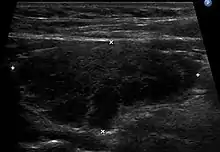

![]() | |

| The thyroid of someone with Hashimoto's thyroiditis as seen with a microscope at low magnification | |